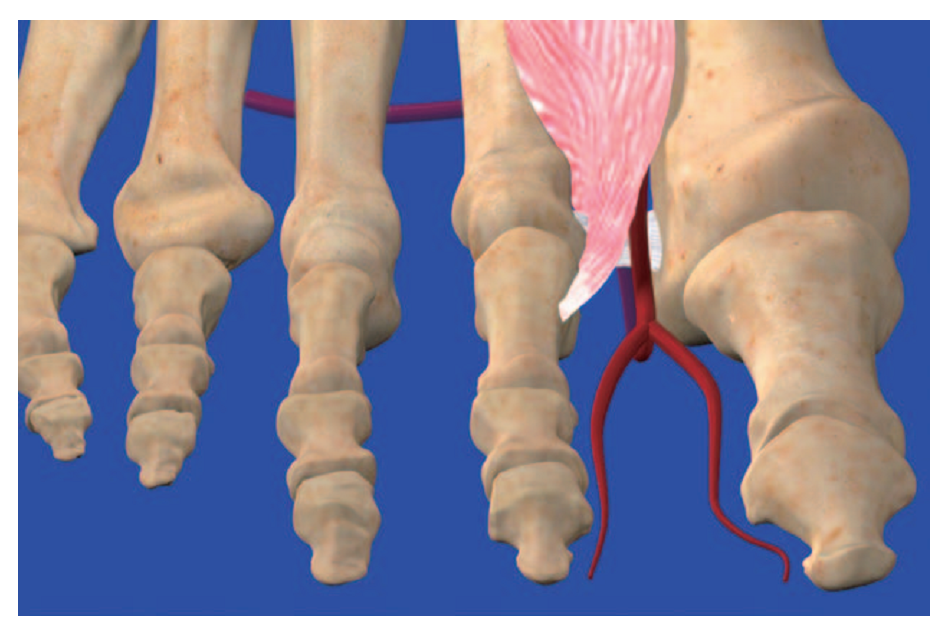

按照第1跖背动脉在跖骨间隙走行情况分为3型。

1、间隙型:第1跖背动脉从骨间背侧肌近端双羽间穿入到骨间背侧肌下方,走行于骨间背侧肌与第1跖骨间隙,逐渐紧贴第1跖骨向远端走行,远端浅出该肌至浅层,记作C1;

C1

2、表浅型:第1跖背动脉走行于骨间背侧肌浅面,记作C2;

C2

3、细小或缺如型,第1跖背动脉在第1跖骨间隙非常细小,血管直径小于0.5mm,对临床手术意义有限,记作C3.

此外,本研究发现第1跖背动脉并不穿过第1骨间背侧肌肌肉内部,而是在第1骨间背侧肌胫腓两头之间,在两头的交汇处绕过第1骨间背侧肌的胫侧头穿入至其跖侧,位于第1骨间背侧肌和第1跖骨体之间的间隙内紧贴第1跖骨体走行。手术中解剖游离第1跖背动脉时,仅需切断第1骨间背侧肌胫侧头,将其向腓侧牵拉翻起,即可清晰显露肌肉与跖骨体之间的第1跖背动脉。